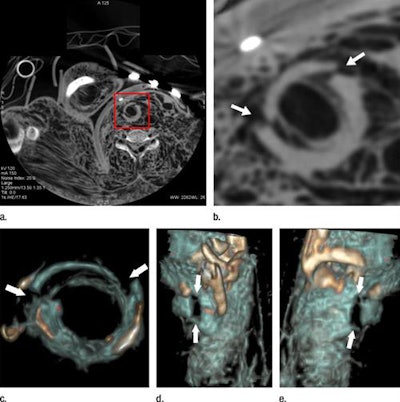

CT angiography might be able to help. In prior research, Grabherr and colleagues demonstrated the potential of using CT angiography instead of standard CT to improve the postmortem visualization of vascular lesions in a small sample population. Their protocol used a pressure-controlled perfusion device (Virtangio, Fumedica) to inject a mixture of paraffin oil and a contrast agent (Angiofil, Fumedica) into the femoral vasculature -- ultimately enabling the visualization of arteries and veins during CT angiography. They suggested that this enhanced imaging could help guide and optimize subsequent autopsy.

Postmortem CT angiography revealed a greater number of findings than conventional autopsy did, even when the cases were divided by type of wound. And this difference was especially pronounced for skeletal and vascular lesions, many of which were not even visible during autopsy.

The radiologist and forensic pathologists detected a statistically significant increase in essential bone and vascular findings using CT angiography compared with autopsy for all of the causes of death (p < 0.001). Specifically, CT angiography led to the discovery of 11.5% more essential vascular lesions in cases of natural death, 39.1% more in cases of localized trauma, 29.9% more in cases of suspected medical error, and 31.4% more in cases of polytrauma.